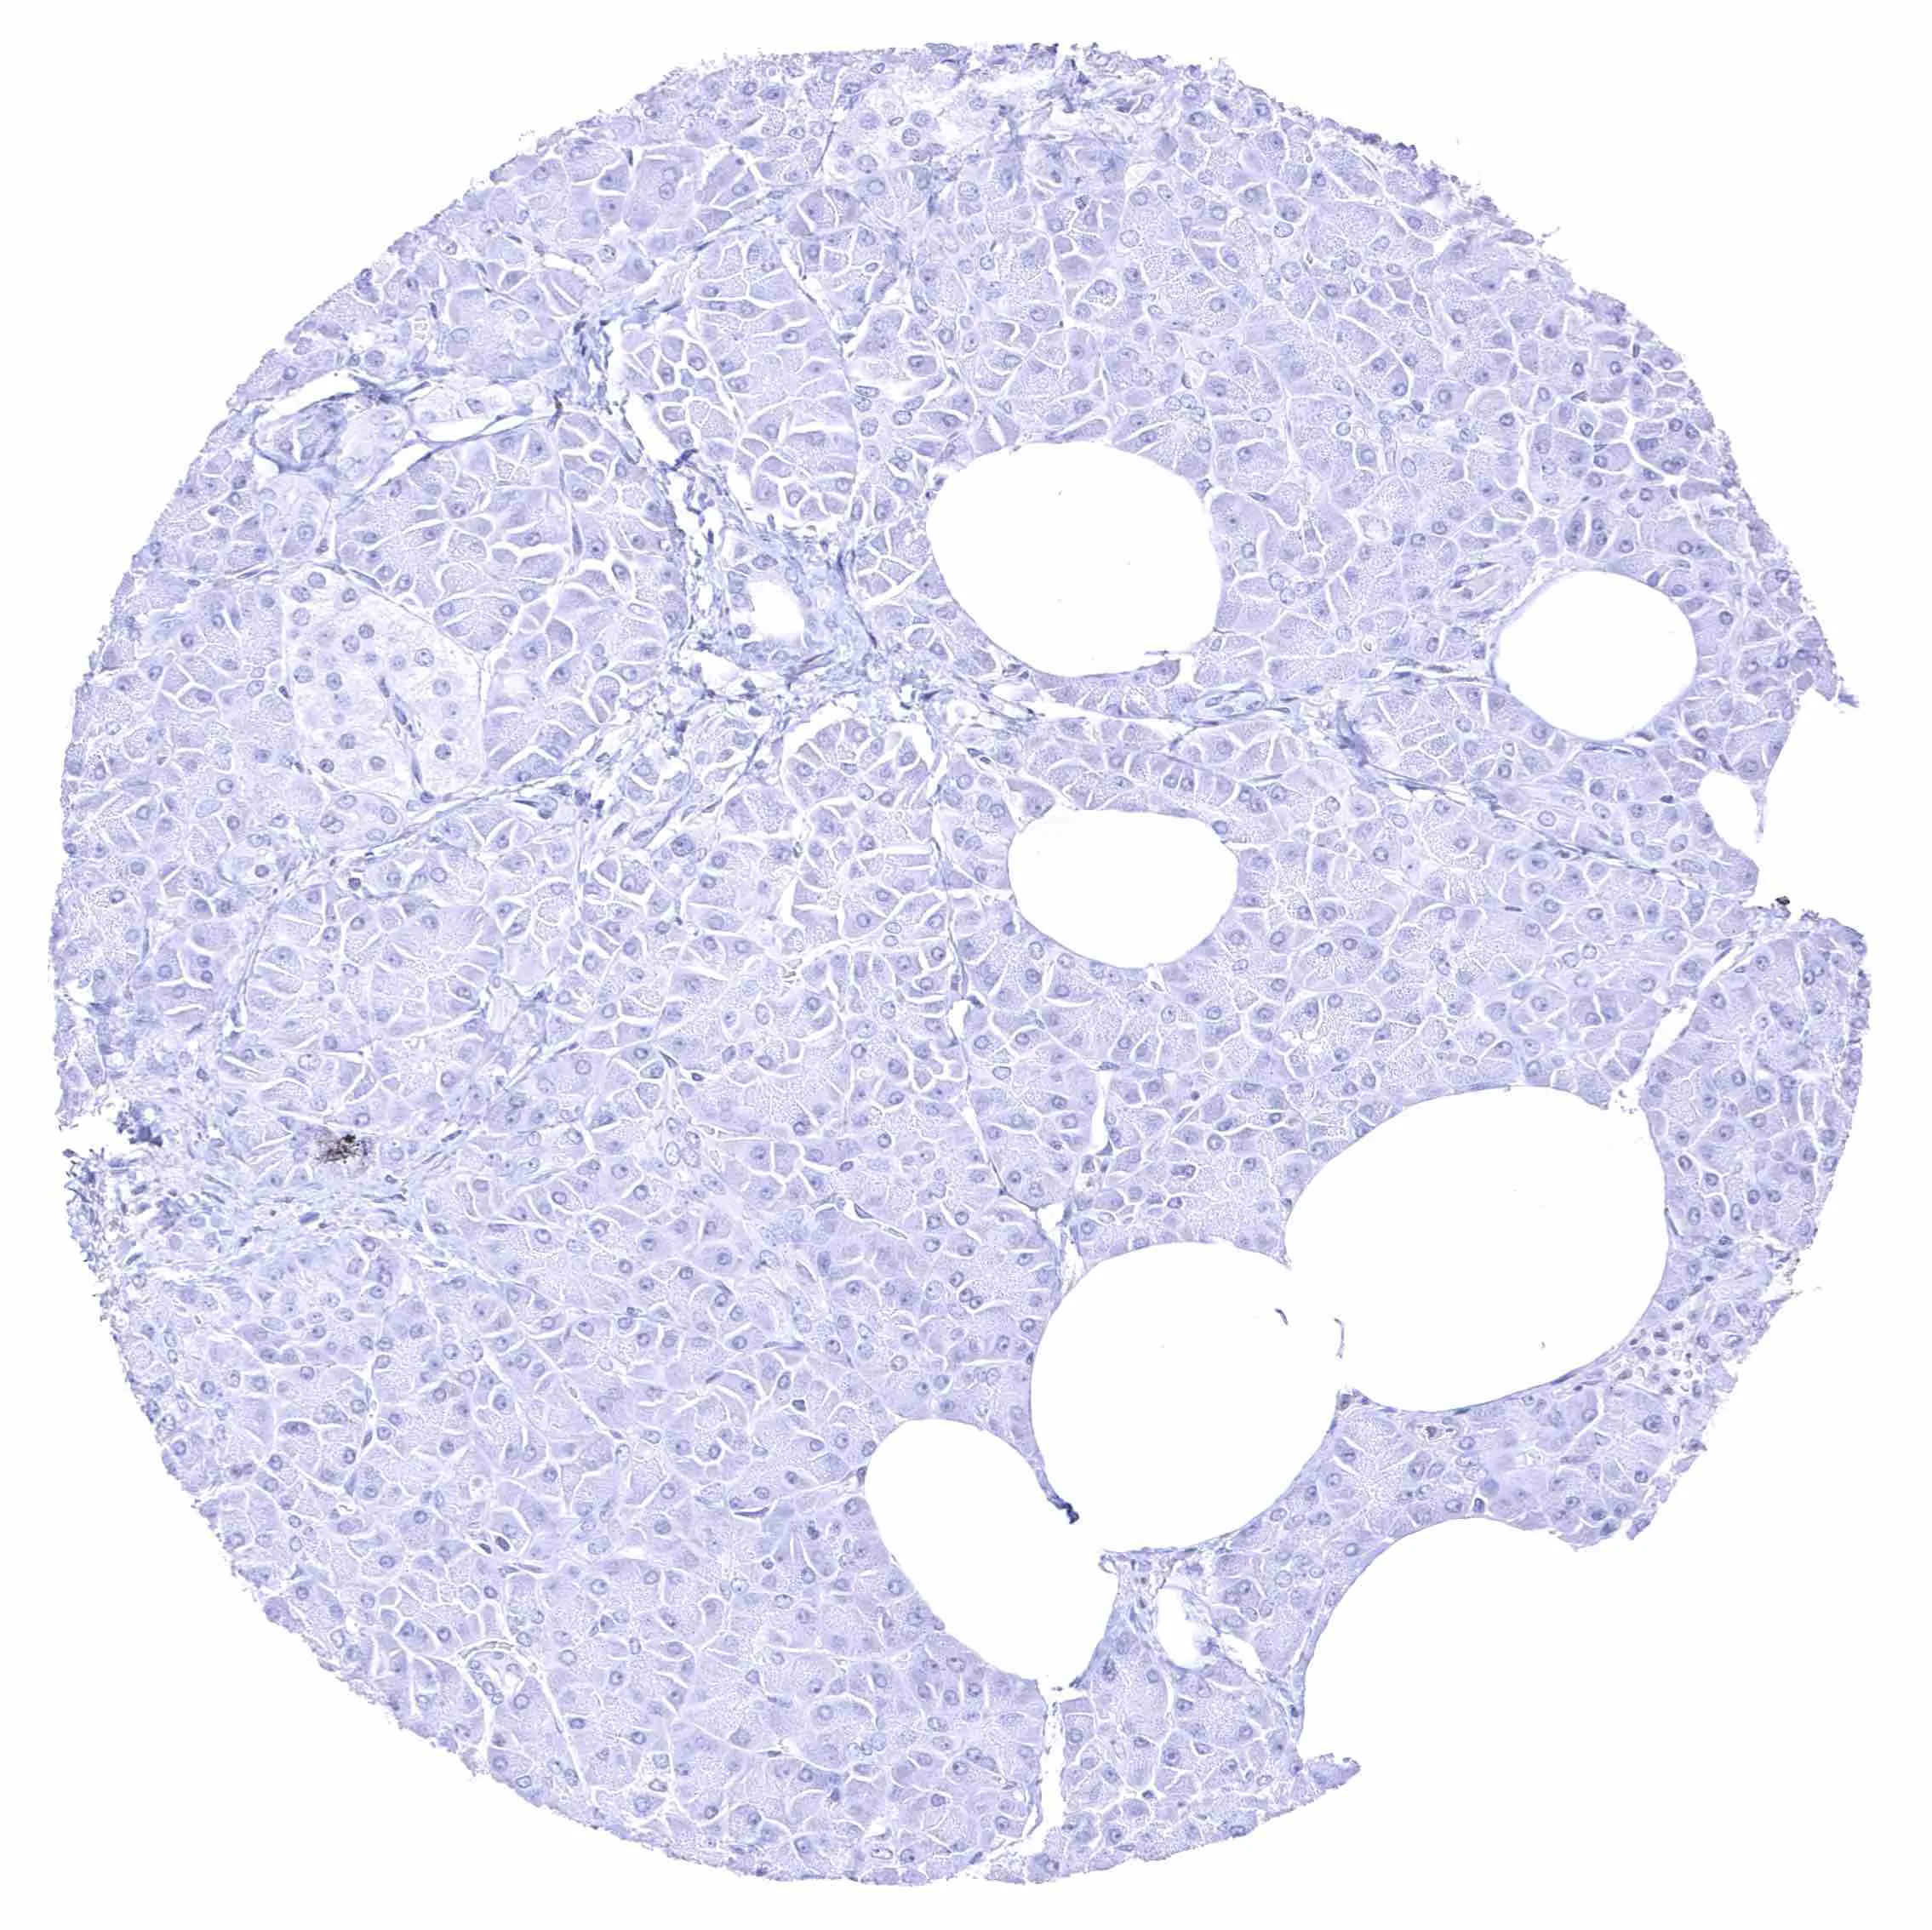

Pancreas